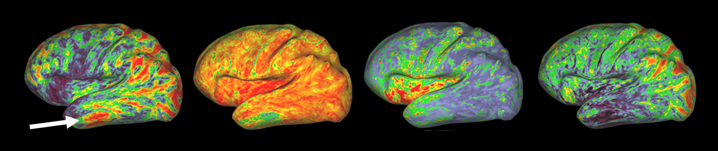

Have a look at my first first-authored paper on Imaging Neuroscience!

Honored to receive a Summa Cum Laude Merit Award and 2nd Prize for Best Oral Presentation from the Diffusion Study Group at ISMRM 2023.

Check out Aunt Minnie Europe's article featuring my work on diffusion MRI and neurological disorders.

I was thrilled to present one of my abstracts in the Proffered Oral session. It was an intense, productive, and inspiring experience with many new research ideas.